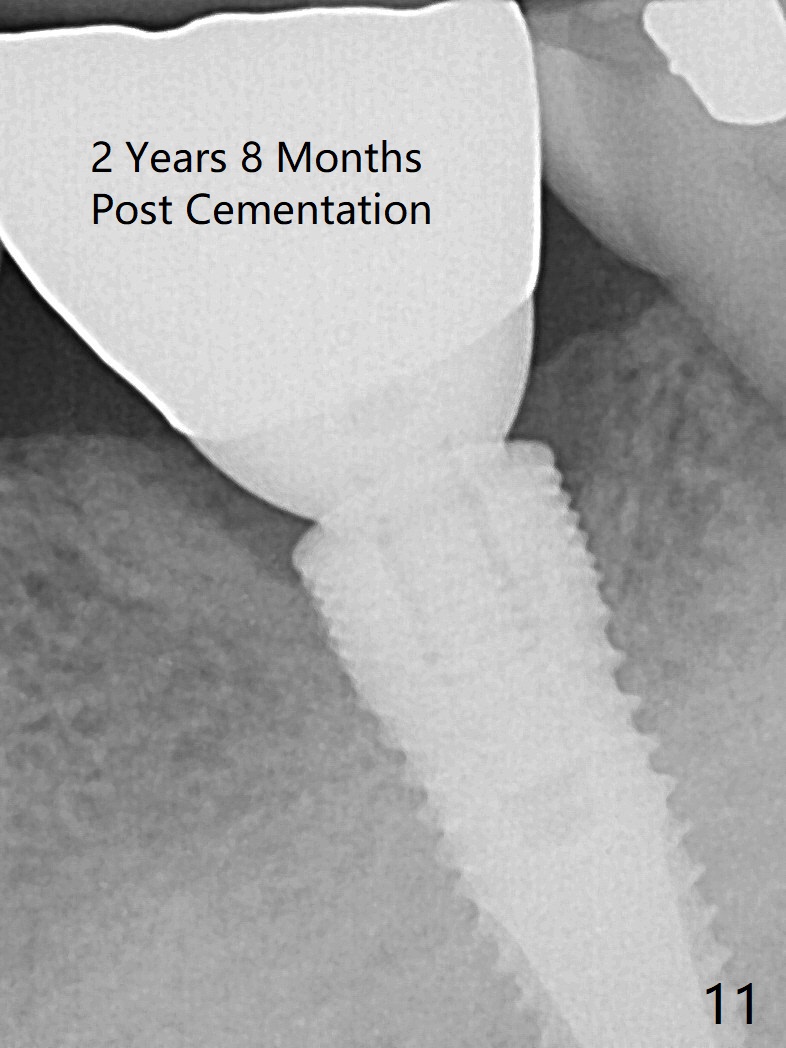

It appears that the loss of the provisional in this case is due to untightening the abutment. The most secure method to fix the abutment/implant in place is to apply setting acrylic to the undercut without taking it out immediately. This is called provisional without cement (1 2 3 4 5). Bone density increases in the peri-implant space 16 months post cementation (Fig.10) and continues to increase 2 years 8 months post cementation (Fig.11).